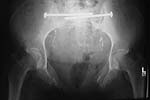

I enclosed a similar injury Xray. Although this patient has anterior SI widening on the left, he has the same anterior ring injury. B rami and a fx-dislocation of the symphysis.

Another way to fix the injury Dr. Reilly showed would be to stabilize the rami fractures with screws instead of plates. You could reduce both ramus fractures and stabilize them with cannulated screws (can be placed either antegrade or retrograde) and then plate the symphysis.

Once the symphsis and anterior ring are fixed, you could assess the posterior ring and see if it needed to be stabilized, too. In this view it looks like it might not need anything once the symphysis is done.

The nice thing about the ramus screws is that you don't have to do as much soft tissue dissection as you would with a plate. You'll have to do something close to a complete ilioinguinal approach to plate that high ramus fracture on the patient's right. The plates should work fine, but if I was that patient, I would rather have a ramus screw and the lesser dissection than a big ORIF with a plate.